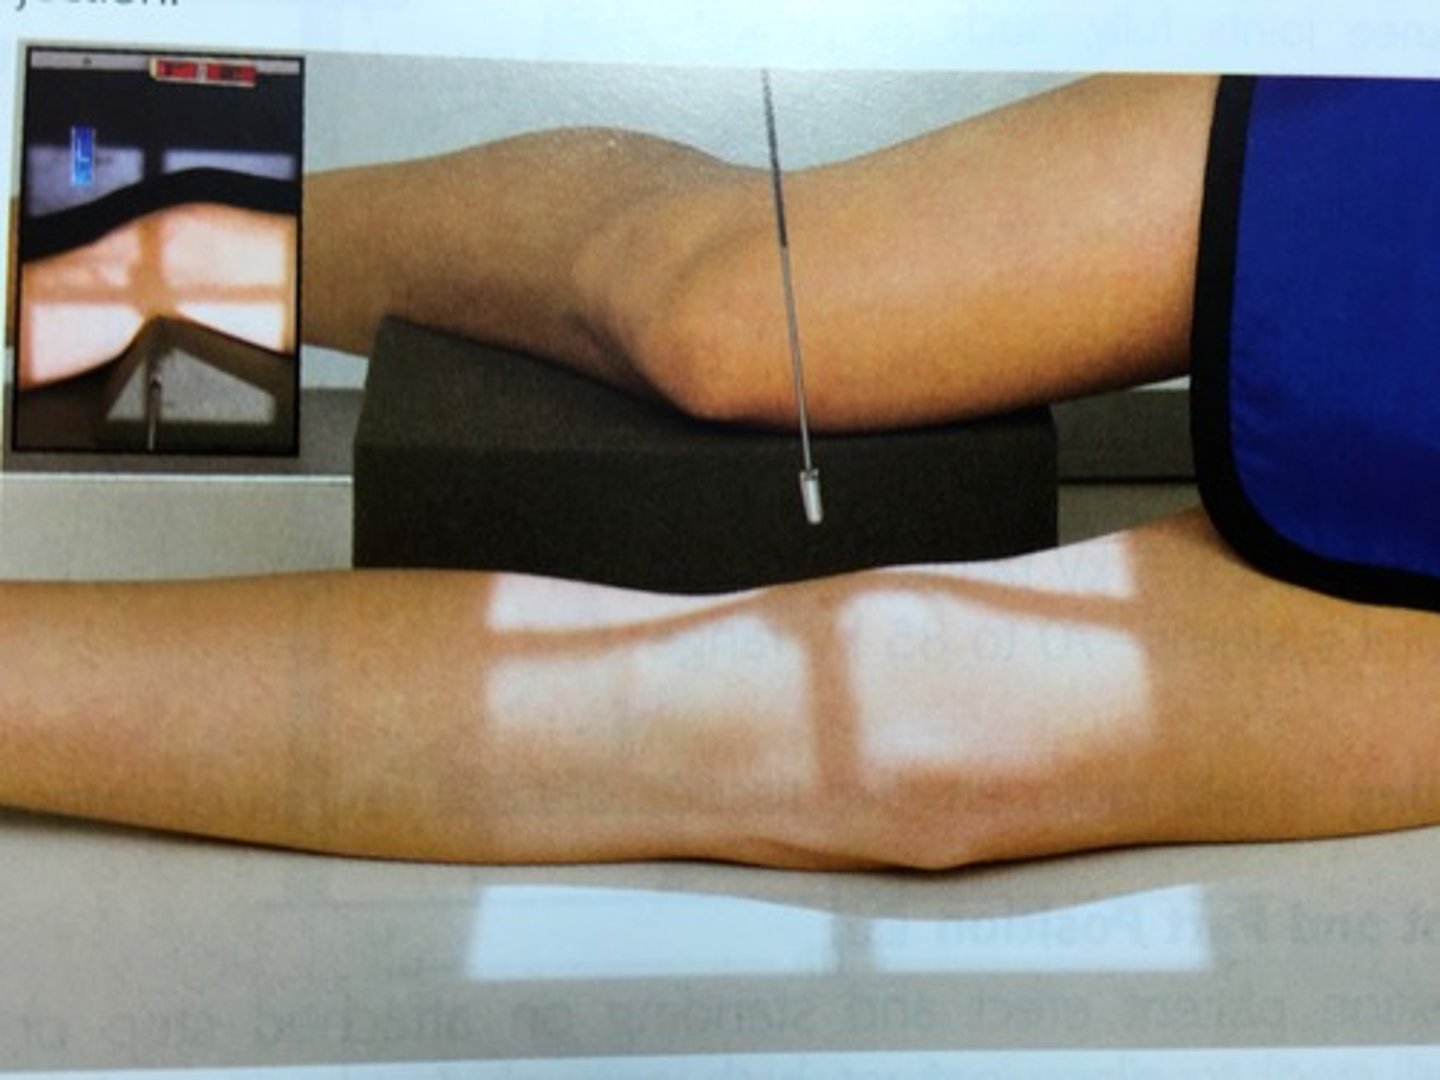

Describe, in the detail, how you would position the PATIENT for a SKYLINE projection of the knee (supero-inferior)

1. The patient sits on the x-ray couch with affected knee flexed over the edge.

2. If possible the knee should be flexed to 45 degrees.

3. Patient to lean back whilst keeping affected knee still to avoid primary beam.

4. The IR should be at the level of the inferior border of the tibial tuberosity